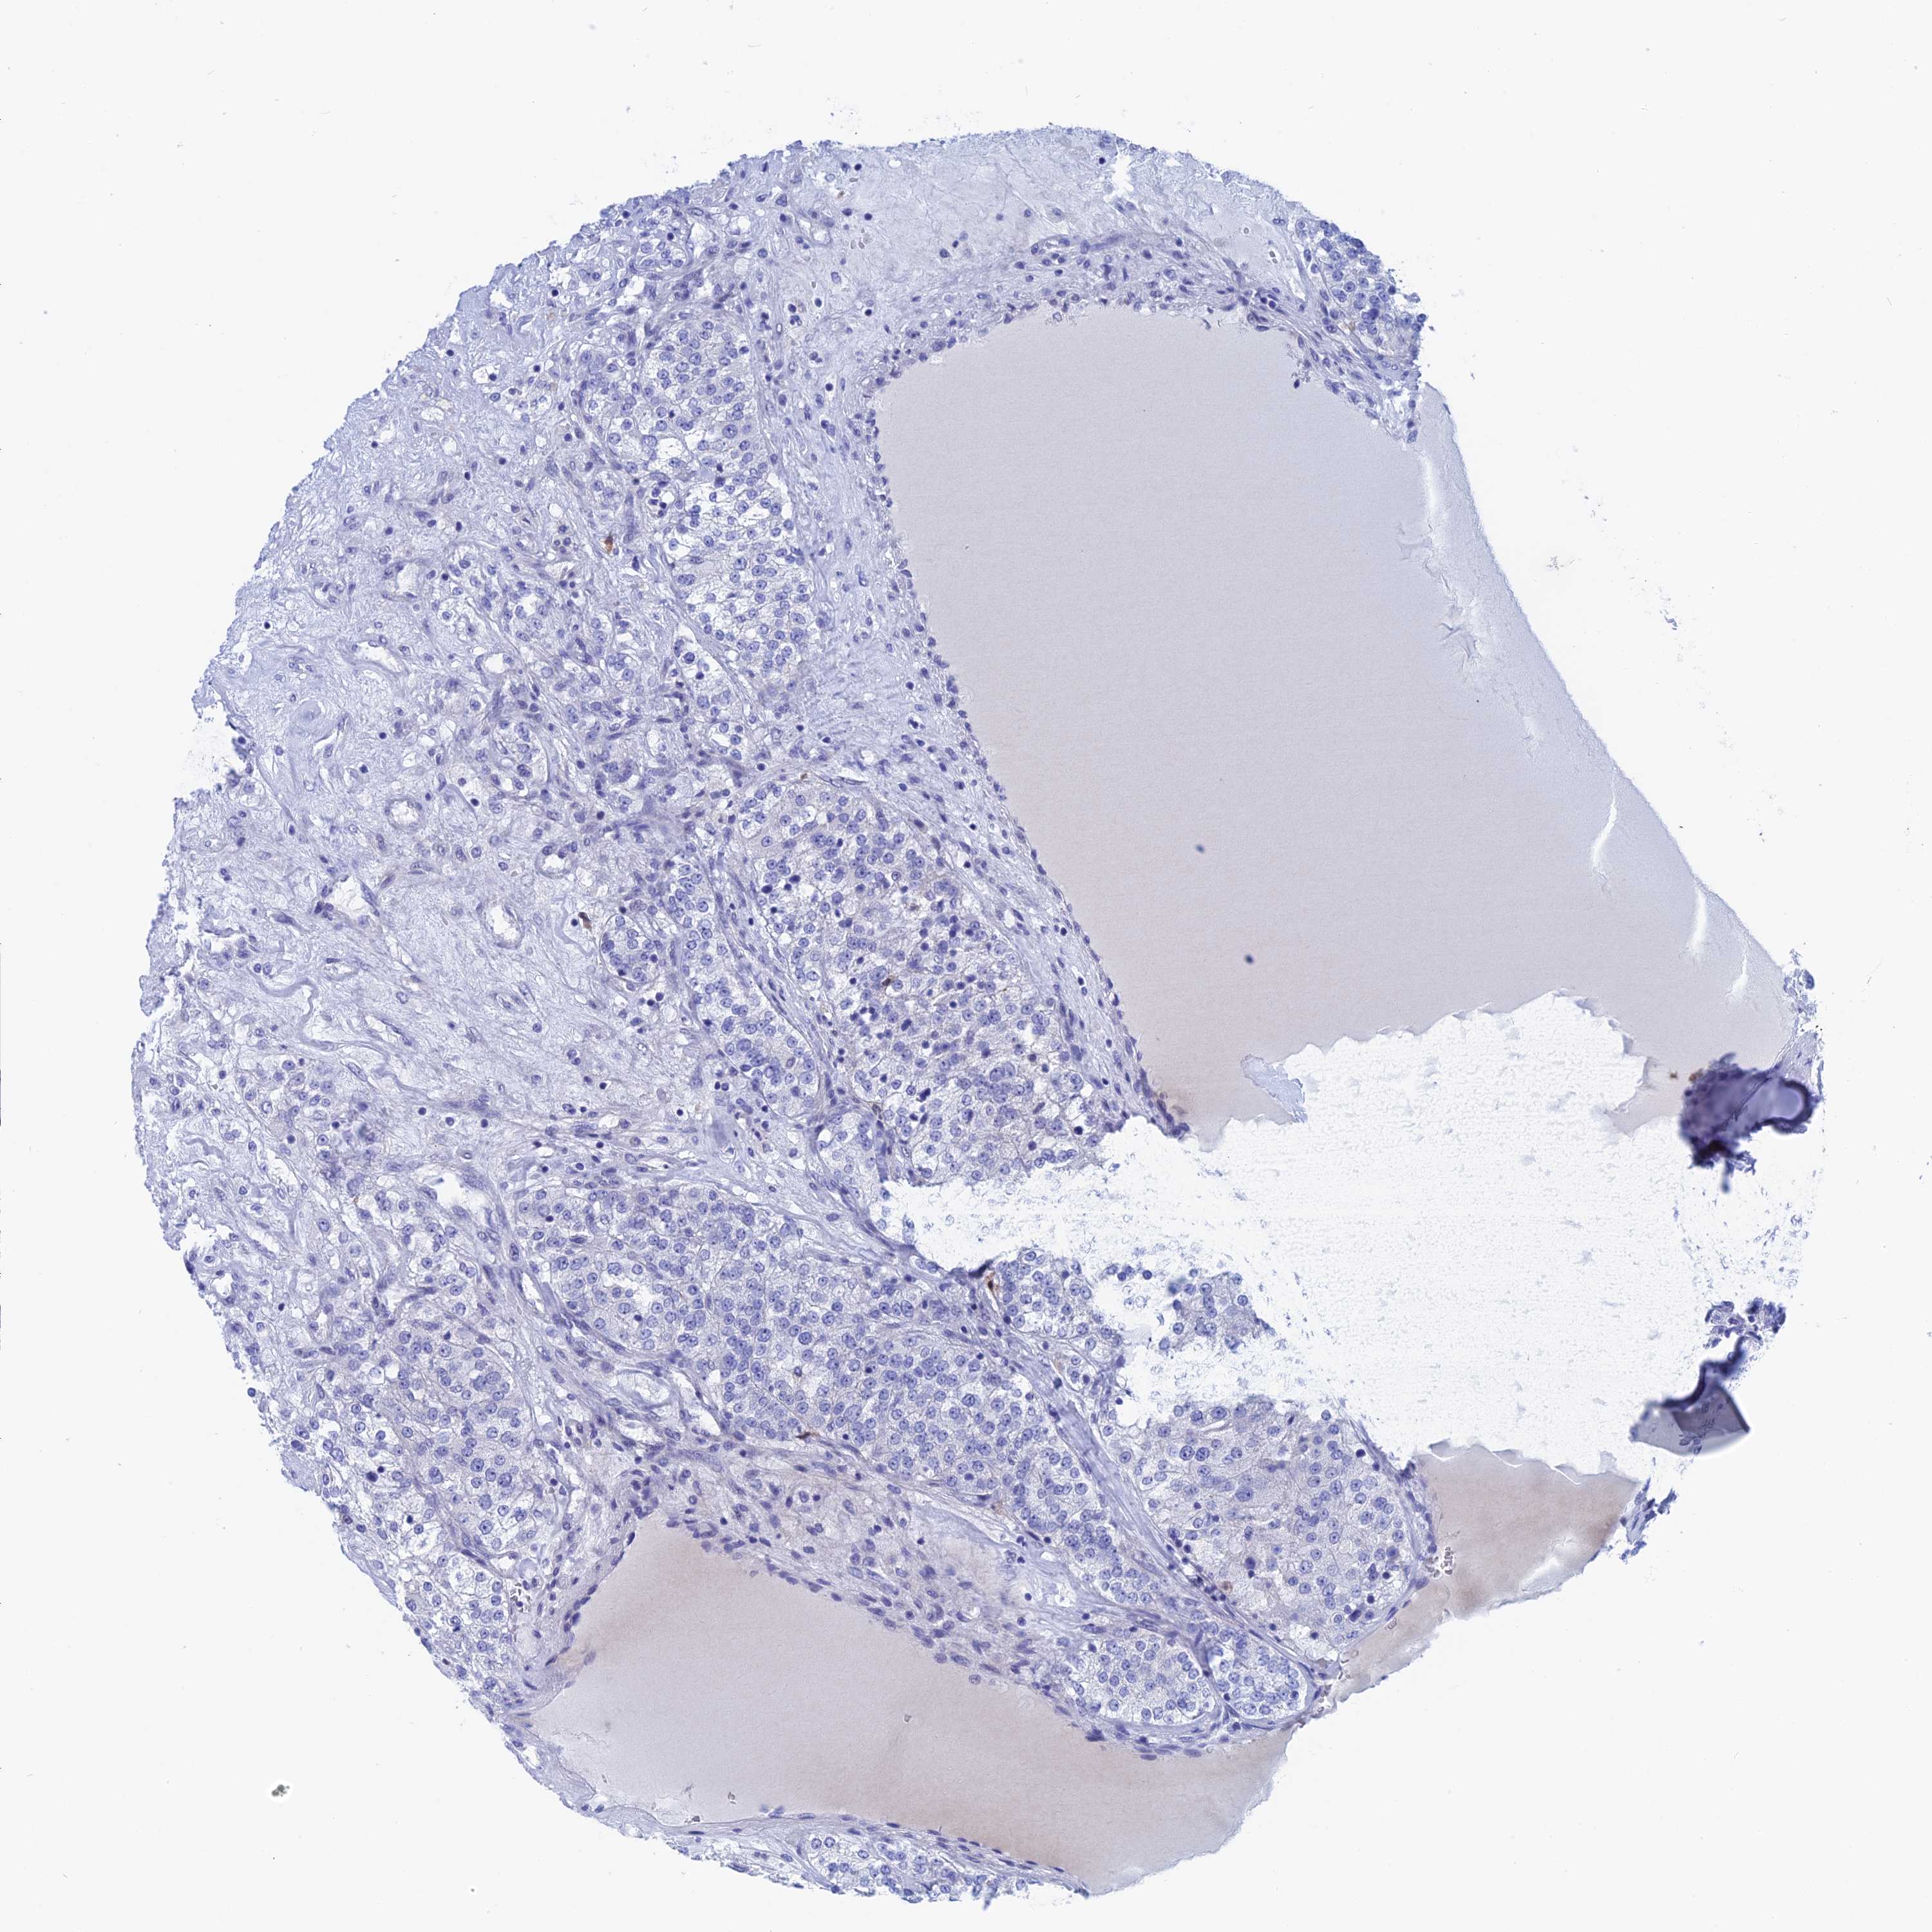

KIDNEY RENAL CLEAR CELL CARCINOMA (VALIDATION) - Interactive survival scatter ploti

The Survival Scatter plot shows the clinical status (i.e. dead or alive) for all individuals in the patient cohort, based on the same data that underlies the corresponding Kaplan-Meier plots. Patients that are alive at last time for follow-up are shown in blue and patients who have died during the study are shown in red.

The x-axis shows the expression levels (FPKM) of the investigated gene in the tumor tissue at the time of diagnosis. The y-axis shows the follow-up time after diagnosis (years). Both axes are complimented with kernel density curves demonstrating the data density over the axes. The top density plot shows the expression levels (FPKM) distribution among dead (red) and alive patients (blue). The right density plot shows the data density of the survived years of dead patients with high and low expression levels respectively, stratified using the cutoff indicated by the vertical dashed line through the Survival Scatter plot. This cutoff is automatically defined based on the FPKM cutoff that minimizes the p-score. The cutoff can be changed by dragging the vertical line or by entering a cutoff value in the square labeled "Current cut-off".

Under the Survival Scatter plot the p-score landscape (black curve; left axis) is shown together with dead median separation (red curve; right axis). Dead median separation is the difference in median mRNA expression between patients who have died with high and low expression, respectively. It is calculated as follows: median FPKM expression of dead patients with high expression - median FPKM expression of dead patients with low expression. This is intended to aid the user in visually exploring custom cutoffs and the associated p-scores and dead median separation.

Individual patient data is displayed and can be filtered by clicking on one or more of the category buttons on the top of the page. Categories describing expression level and patient information include: high, low, alive, dead, female, male and tumor stages. The scale of the x-axis can be toggled between linear and log-scale by clicking on the "x log" button. Mouse-over function shows TCGA ID, patient information and mRNA expression (FPKM) for each patient.

& Survival analysisi

Kaplan-Meier plots summarize results from analysis of correlation between mRNA expression level and patient survival. Patients were divided based on level of expression into one of the two groups "low" (under cut off) or "high" (over cut off). X-axis shows time for survival (years) and y-axis shows the probability of survival, where 1.0 corresponds to 100 percent.

WDR83 is not prognostic in Kidney Renal Clear Cell Carcinoma (validation)

Best expression cut offi

Based on the FPKM value of each gene, patients were classified into two groups and association between prognosis (survival) and gene expression (FPKM) was examined. The best expression cut-off refers the FPKM value that yields maximal difference with regard to survival between the two groups at the lowest log-rank P-value. Best expression cut-off was selected based on survival analysis .

When clicking on this number, the vertical dashed line indicating cut-off, the interactive survival plot, and the Kaplan-Meier curve will be adjusted to show results based on the best expression cut-off.

: 6.14

P scorei

Log-rank P value for Kaplan-Meier plot showing results from analysis of correlation between mRNA expression level and patient survival.

N/A

TCGA RNA samplesi

RNA-seq data is reported as average FPKM (number Fragments Per Kilobase of exon per Million reads), generated by the The Cancer Genome Atlas (TCGA) .

Normal distribution across the dataset is visualized with box plots, shown as median and 25th and 75th percentiles. Points are displayed as outliers if they are above or below 1.5 times the interquartile range. FPKM values of the individual samples are presented next to the box plot.

Average pTPM 7.2

Number of samples 100